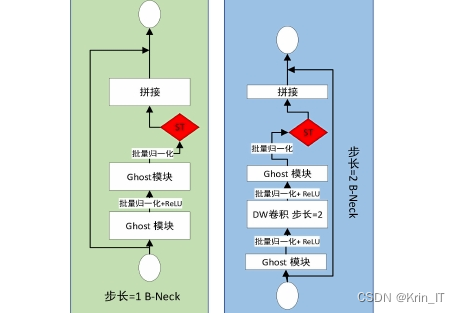

在主干网络的改进方面,原版YOLOv5的主干网络部分大体保留了YOLOv4的结构,但CSPDarknet53由于参数量庞大,对计算机的存储和计算能力要求较高,进而影响了运行速度。为了解决这一问题,研究参考了Ghost bottleneck结构,对其进行了改进。新的Ghost bottleneck结构中引入了前述的时空注意力机制,尽管增加了部分参数,但这一机制是为了适应肺部CT影像中可能出现的多种肺结节而专门设计的,从而能够更准确地提取特征信息。尽管整体计算量有所增加,但相较于YOLOv5原有的CSPDarknet53结构,其计算复杂度仍然显著降低。改进后的Ghost bottleneck结构(简称G-BNeck)通过增强特征提取能力,进一步提升了模型在复杂任务中的表现。

以YOLOv5的主体结构为基础,首先将骨干网络部分更改为改进的Ghost bottleneck(G-Bneck)结构,这一改动使得网络更加轻量化,提升了运行效率。随后,在G-Bneck中引入了时空注意力机制,以减少冗余信息对识别效果的影响,增强了模型对关键特征的关注能力。结合SPP结构与FPN(特征金字塔网络)和PAN(路径聚合网络),构建了一个特征深度融合提取网络,实现对目标特征的详尽提取。最终,通过这一改进的网络结构输出预测结果,完成了算法的构建任务。